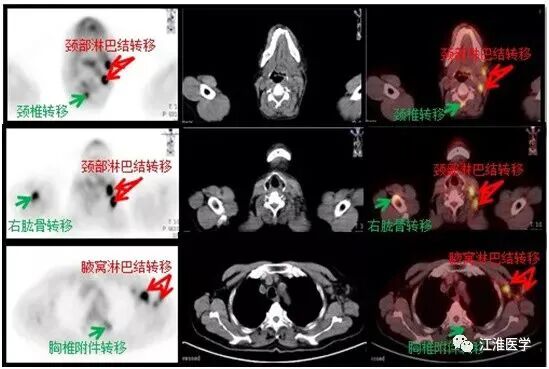

口腔科的医生推荐去找肿瘤科,我查了病人,给他儿子说,老人10年前已经有恶性表现,现在颈部、腋窝已经摸到了很多淋巴结,估计已经转移,患者全身酸痛可能骨头已经有了转移。

老张的结果,可想而知,下面的图诉说着血淋淋的故事:

图中左侧的黑白图除了大脑,心脏和膀胱外其余的黑点全是肿瘤病灶,右边的十字指示的是腮腺的复发的恶性肿瘤